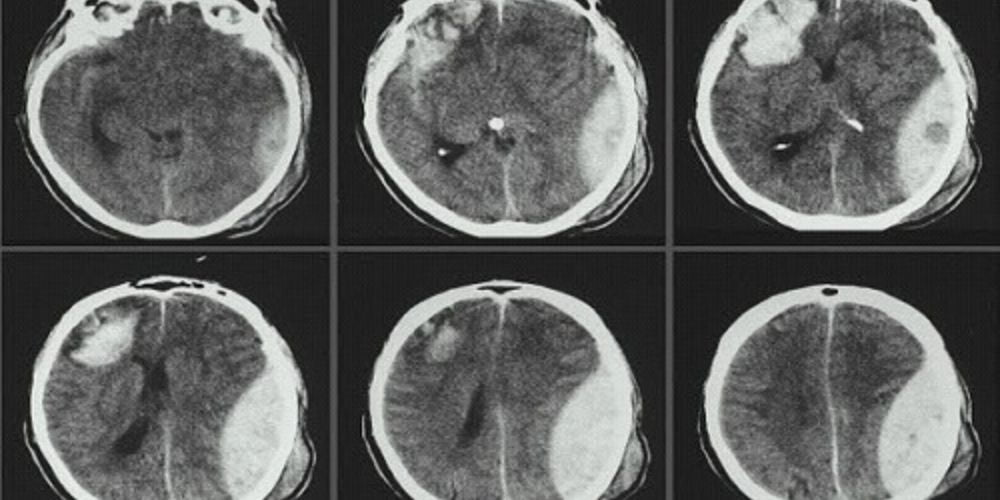

Ví dụ, ảnh y tế có thể là phim X-quang phổi phát hiện lao hoặc MRI não phát hiện u. Đây là sự kết hợp giữa vật lý, công nghệ và y học để tạo chẩn đoán chính xác. Ảnh y tế là hành trình nhìn xuyên qua cơ thể, nơi mỗi pixel là một thông tin sống còn.

Tạo “pattern recognition”: Vùng sáng (vôi hóa), vùng tối (khí, dịch).

Áp dụng “red flag list”: Gãy xương, tràn dịch màng phổi, khối u >3cm.